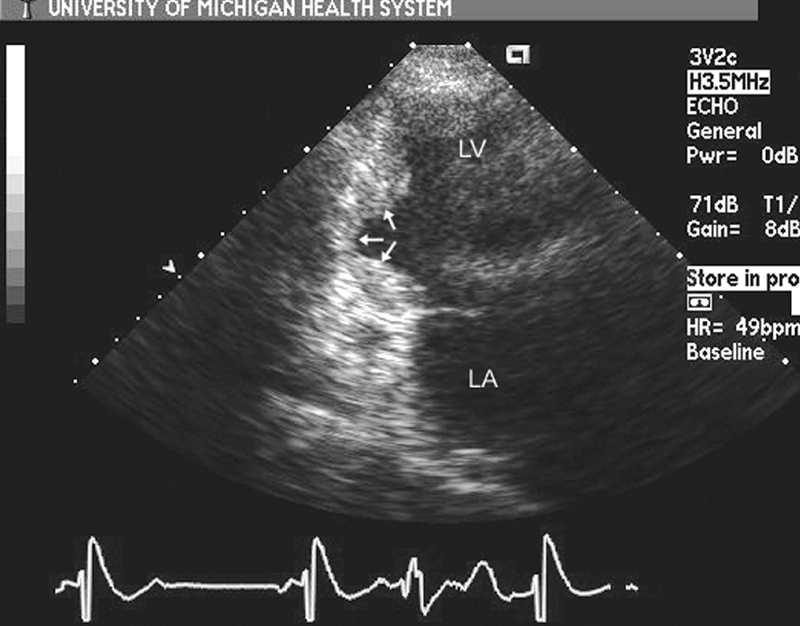

فحوصات تشخيصية لبعض امراض القلب والشرايين التاجية